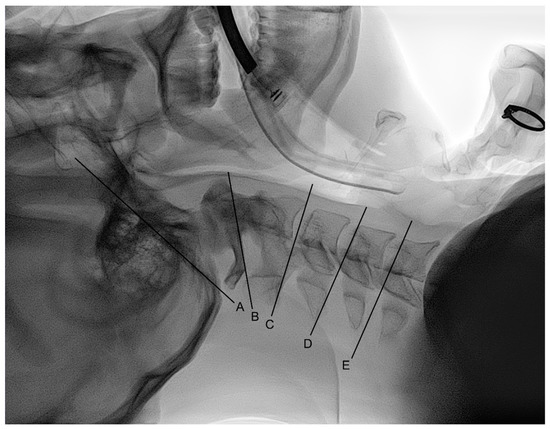

2.4. Measurement

2.5. Outcomes